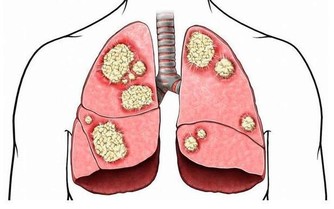

7.善感多疑,總是懷疑自己有大病,雖然不斷進行各種檢查,但仍難釋其疑。

11.經常厭食、噁心、腹脹或腹瀉,或出現胃痛等症狀,但是檢查時又無明顯的器質性改變。

15.自感頭痛、腰痛、身痛,而又查不出器質性的病因。